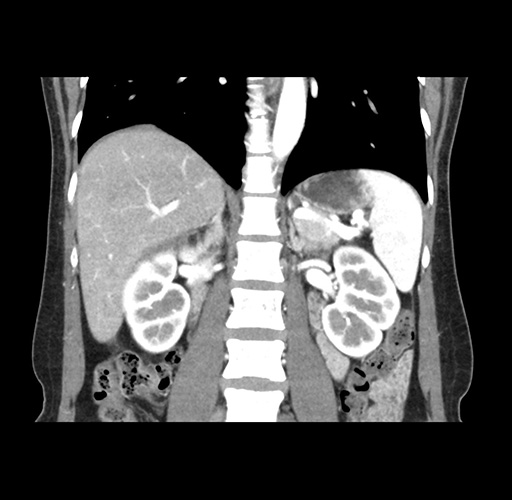

Imaging Analysis

Look through the patient's CT scan to identify any areas of concern for the necessary procedure.

Based on your CT findings, which issue(s) would give reason for "planned slowing down moment(s)" in this case?